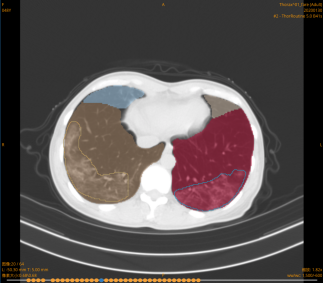

四、新冠肺炎AI阅片系统上线

国家卫健委《新型冠状病毒感染的肺炎的诊疗方案》将CT影像纳入诊断标准之一。

随着疫情防控形势的发展,大量疑似病例出现,爆发式需求让一线医生不堪重负。由于新冠肺炎核酸检测假阴性比率高,影像鉴别难度大,严重影响了新冠肺炎的快速识别诊断。在这种形势下,如何借力AI,进行新冠肺炎CT影像的鉴别诊断对于实现早诊断、早隔离、早治疗意义重大。

信息科协助设备科、放射科,完成了我院BioMind “新冠”肺炎CT影像AI定性辅助诊断系统的上线工作。

随着AI 辅诊系统的上线,不仅能够实现“肺炎诊断”,还能实现新冠肺炎与其他肺炎(病毒性肺炎、细菌性肺炎等)的进一步鉴别诊断。该系统全程仅需十几秒且针对新冠肺炎的诊断结果与核酸检测阳性结果符合率超过95.5%。